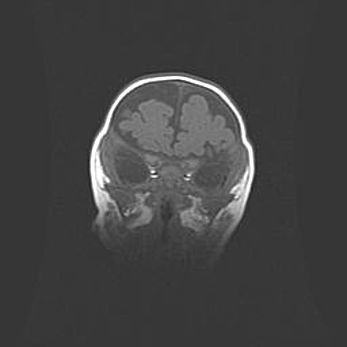

Сообщающаяся гидроцефалия. Кистозная энцефаломаляция головного мозга.

Возраст: 3 месяца 4 дня

Вес: 3100 г

Пол: женский

Окружность головы: 34 см

Срок гестации: 31 неделя

Кистозная энцефаломаляция головного мозга - одна из форм поражения головного мозга в детском возрасте. Характеризуется возникновением множественных и распространённых кист в коре, белом веществе и подкорковых образованиях головного мозга у плодов, новорождённых и детей раннего возраста. Развитие кистозной энцефаломаляции связано с внутриутробной асфиксией и гипотонией, родовой травмой, тромбозом синусов, пороками развития сосудов, инфекциями, сепсисом и другими причинами. Наиболее значимые инфекционные агенты: вирусы простого герпеса, цитомегалии, краснухи, токсоплазмы, энтеробактерии, золотистый стафилококк и другие.